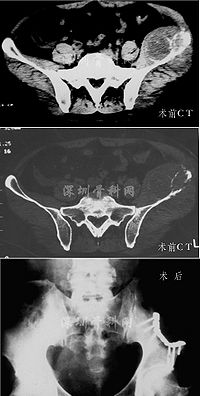

少数情况下,当肿瘤贴近骨骼时,可能显示浅表性骨质溶解或骨膜反应。骨扫描检查对邻近的骨反应很敏感。很少见到病灶的钙化和骨化,但有时也可在肿瘤周围或肿瘤内见到。血管造影可显示其与其他恶性肿瘤所共有的变化。但有时甚至在非常大的肿瘤内,可因组织坏死和出血,而呈现为无血管的影像。主要血管可能移位和受压,但很少被浸润。CT和MRI显示为实心的,非均质性肿块。有时可见大的含有液体的囊腔。

病灶呈灶样缺损的透亮区,多有完整边缘,好发于干骺端,经常可见有皮质破坏,并穿透到软组织中去。无明显骨膜反应。X线征象类似于其他原发或继发的恶性肿瘤,无特征性,全身骨扫描和CT检查有助于肿瘤鉴别的来源为髓内或骨外。